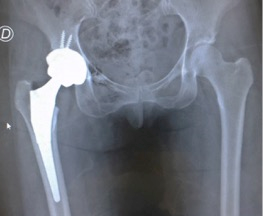

De estos, tres requirieron artroplastia total de cadera (2.63%), y uno (0.87%) se realizó una revisión (figs. 3, 4 y 5). En tres oportunidades se trataba de pacientes con un grado 2 de Tönnis y el restante presentaba un grado 1. Al analizar la relación entre reoperación y el grado 1 y 2 de Tönnis, se encontró un incremento estadísticamente significativo en este último grupo (2.04% versus 25%; p=0.02).

Figura 5: Nueve meses postoperatorios. Se realizó la artroplastia total de cadera.